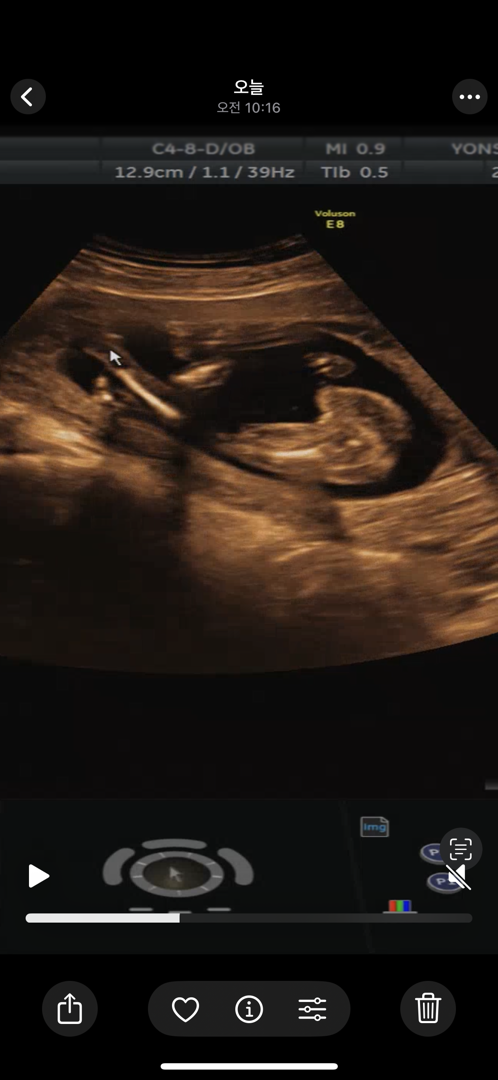

17주 성별

분만병원, 서브병원 둘다 딸같다고 하셨는데 반전될 확률은 없겠죵..?